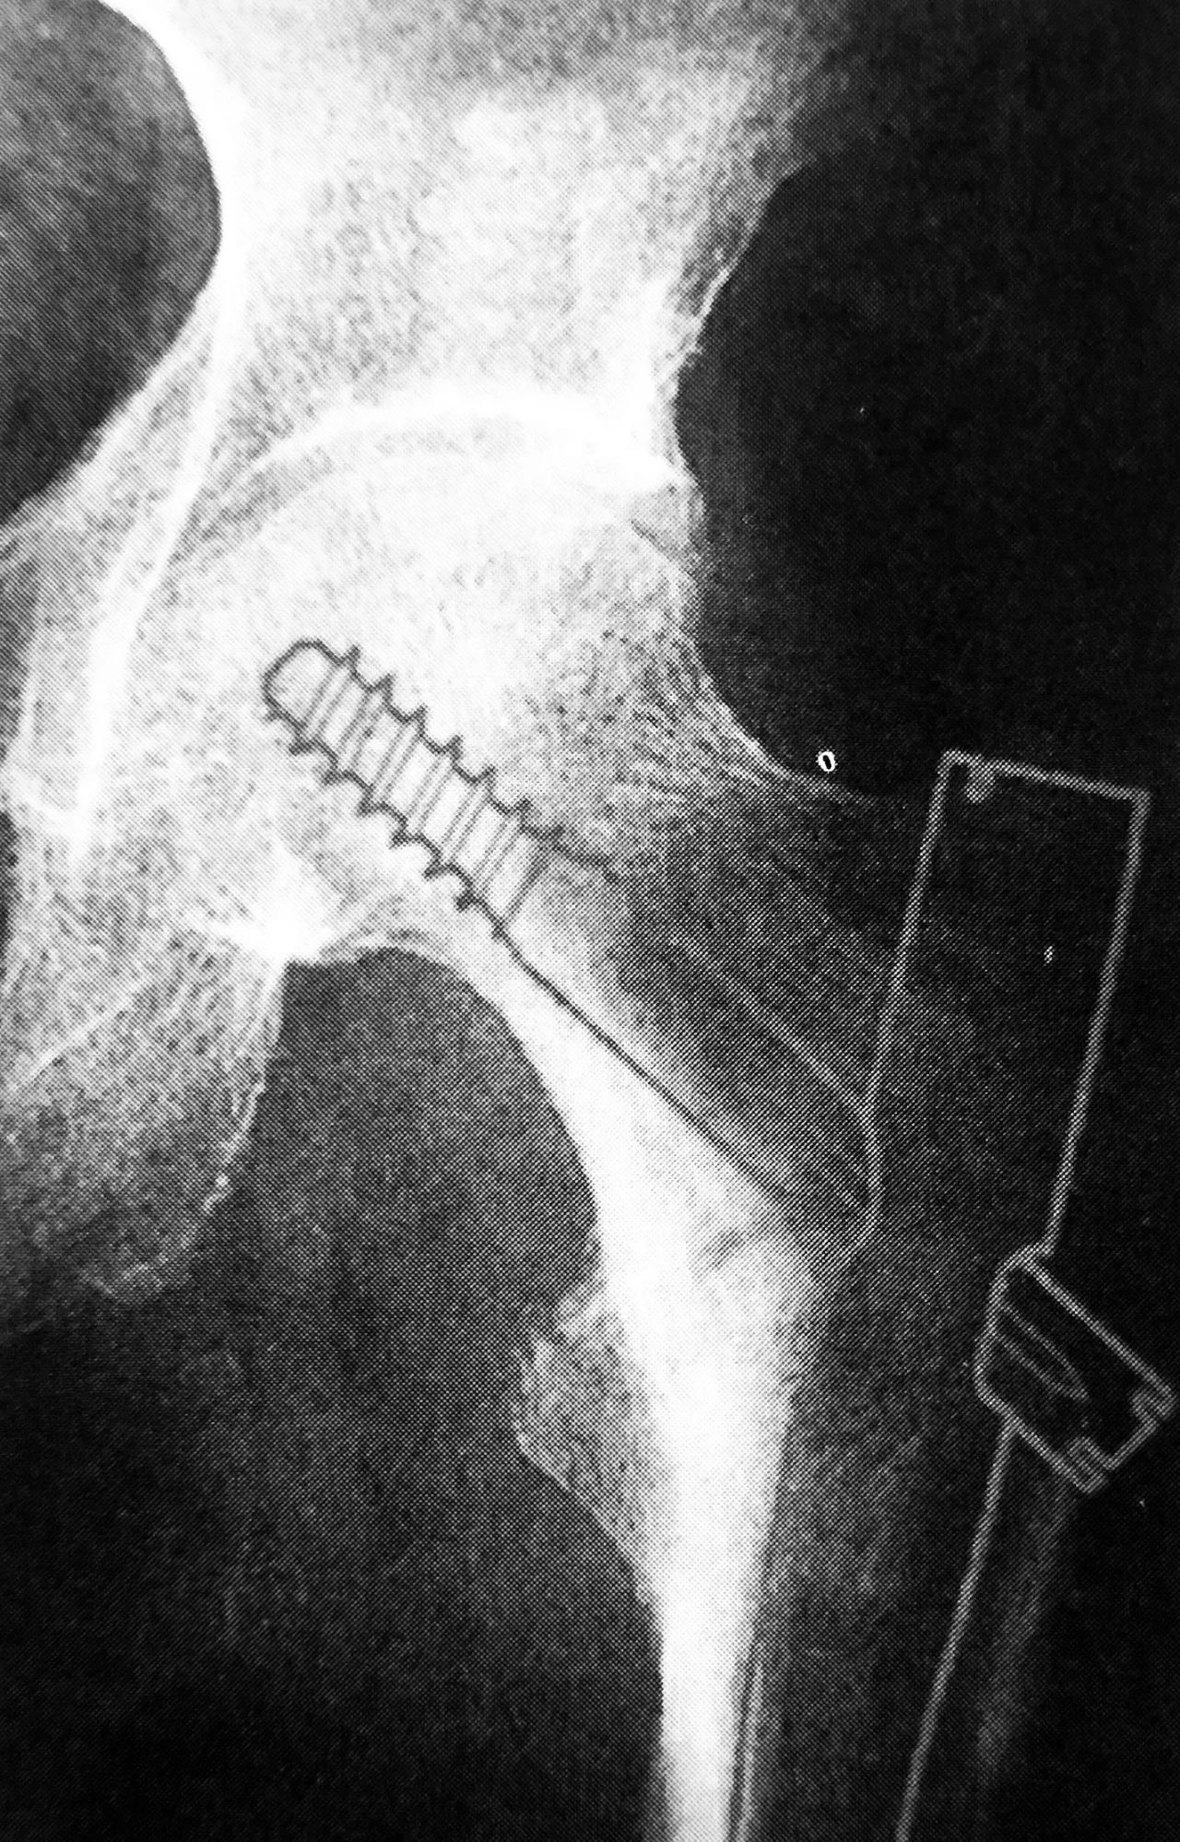

1. Gamma 钉

Gamma 钉适用于股骨颈基底至小转子水平以上的各种类型的骨折。Gamma 钉内固定技术除感染外无绝对禁忌证,伴有严重骨质疏松患者术后的早期活动需要一定的限制。

拉力螺钉的正确放置非常重要,其前提是首先安放好导针的位置,即正位必须与股骨颈轴线重叠或位其稍下方,侧位或斜位导针应在股骨颈中心。

A 拉力螺钉的安装;B 拉力螺钉的正确位置

拉力螺钉的置入,A 确定长度;B 阶梯钻钻孔 C 拧入拉力螺钉并加压

4. 股骨近端髓内钉

股骨近端髓内钉系统( proximal femoral nail system,PFN)是由AO内固定学会根据 Gamma钉原理改良设计而研制的用于股骨近端骨折治疗的髓内固定材料。PFN 适用于股骨颈基底至小转子以下 5cm 的骨折,也就是 AO 分类中 31-A的所有骨折和转子高位股骨干骨折。

其结构特点和优势:①主钉长 240mm,近端直径17mm,远端直径有10、11、12 三种规格可供选择;颈干角设计 130°,外翻角6°

②股骨头、颈内的螺钉有两枚组成,下方为直径 11mm 的主拉力螺钉,上方为直径 6.5mm 的防旋螺钉。这种防旋螺钉的设计能更有效的防止骨折断端的旋转。

③主钉远端可屈性的凹槽设计,远端锁钉孔距钉尖距离较长,最大程度地减少应力集中,降低主钉末端股骨干骨折的风险。

④主钉远端提供静态和动态两个锁钉孔。

PFN 主要并发症是防旋螺钉的向内侧切出近端静态交锁钉或向外退出,被称为「Z效应」。建议拉力螺钉的放置于股骨头软骨面下 0.5cm 以内,防旋钉钉尖与拉力螺钉钉尖位于同一水平线。同时拉力螺钉应尽量下移,贴近股骨距,以增加螺钉在骨质中的锚合力。